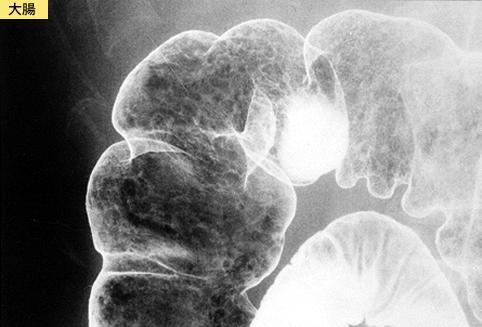

疾病(病理主体)的分类炎症性・溃疡性疾患/消化管淀粉样变性

部位(按器官分)大肠/占据大肠的2个以上区域

检查方法X线